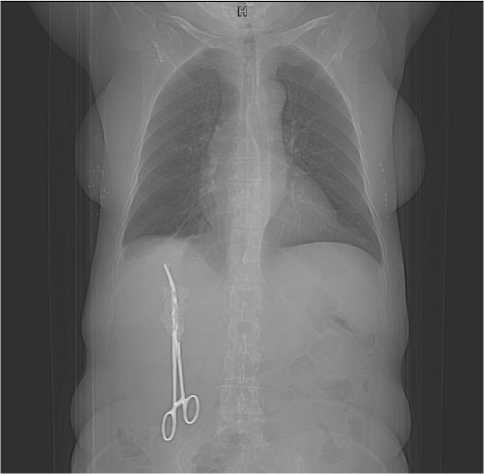

В 2019 г. обратилась к врачу по месту жительства с болями в поясничном отделе позвоночника, при рутинном R-исследовании был обнаружен металлический инородный предмет в правой половине брюшной полости – хирургический зажим. Несмотря на разъяснения хирургов о возможных рисках и осложнениях, пациентка отказалась от предложенного планового оперативного удаления инородного тела, сославшись на отсутствие беспокоящих симптомов.

На последующем КТ-исследовании брюшной полости чётко визуализировано инородное тело подпечёночного пространства со сформированным абсцессом брюшной полости (рис. 4, 5).

Рисунок 4. КТ-визуализация инородного тела (хирургического зажима) брюшной полости

Figure 4. CT imaging of a foreign bode (surgical clamp) in the abdominal cavity

Рисунок 5. КТ-визуализация инородного тела (хирургического зажима) брюшной полости

Figure 5. CT imaging of a foreign bode (surgical clamp) in the abdominal cavity